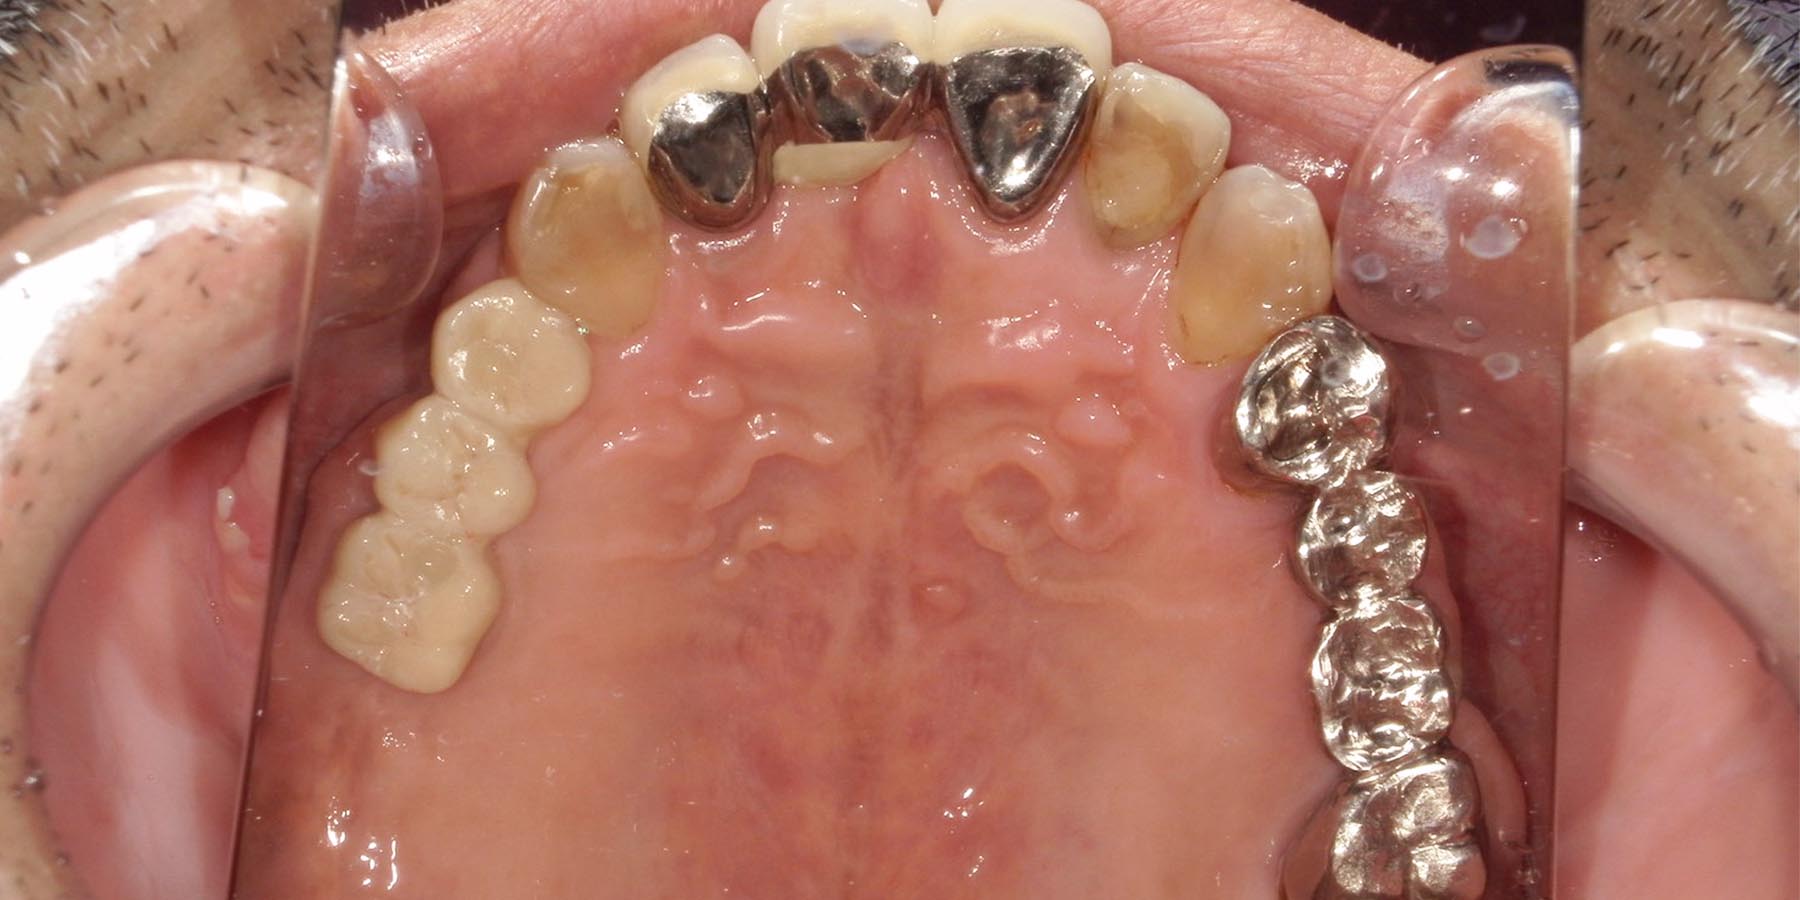

治療後